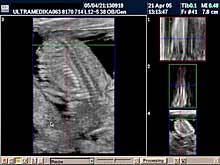

B) II trimestar trudnoće

od 16 do 24

nedelje gestacije

(4 - 6 meseca):

Indikacije za ultrazvučni pregled:

- GENETSKI SONOGRAM

(15-16 nedelja gestacije - 4. mesec):

Otkrivanje ultrazvučnih (soft) markera (markeri koji nisu prisutni u

i trimestru

trudnoće) na postojanje hromozomskih anomalija. Ovaj ultrazvučni

skrining se radi 15- 16 nedelji gestacije u ranom II trimestru

trudnoće. Sam otkriva oko 91% plodova sa aneuploidijama.

- SKRINING NA ANATOMSKE ANOMALIJE:

- registrovanje i procena

ultrazvučnih markera koji ukazuju na postojanje adekvatno završenog

formiranja organa ploda (embriogeneze).

Većina plodova sa poremećenom embriogenezom i postojanjem anatomskih anomalija (mozga, kičme, srca,

pluća, organa stomaka, prednjeg trbušnog zida,udova itd) se može

otkriti jedino ultrazvukom.

- 3D Sono CT SRCA PLODA (fetalna ehokardiografija) Prostorno, vremenska

korelacija ultrazvučnih markera prikazana multiplanarno predstavlja

dopunsku metodu u otkrivanju urođenih srčanih anomalija.

Napomena:

a)

Urođene srčane mane su 6 puta češće od hromozomskih anomalija i

njihova težina često zahteva prekid trudnoće. b)

Ovaj pregled je posebno registrovan za trudnoće koje su prethodno

imale plod sa srčanom manom ili kada u okviru standardnog pregleda

nisu dobijene sve validne ultrazvučne informacije radi pouzdanog

isključenja njihovog postojanja.

Mada je prva procena anatomije srca obavezna u I trimestru trudnoće,

konačna procena se mora završiti od 16 do kraja 24 nedelje gestacije

(6 meseci). Nakon toga procena osnovne anatomije je otežana i

rezervisana je za procenu hemodinamike srca!